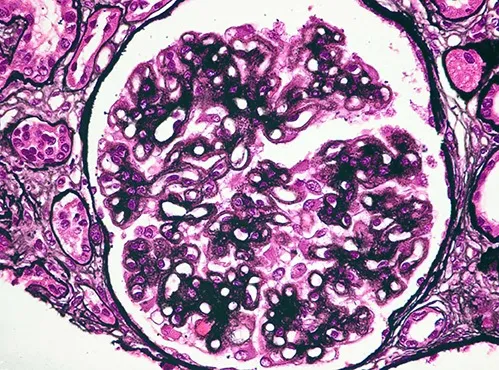

Doação renal em mulheres jovens pode impactar mais o feto do que a mãe — e esse dado muda o pré-operatório. O maior estudo já feito mostra aumento de PIG e sinais de disfunção placentária silenciosa, especialmente em nulíparas. Se você ainda não discute isso de forma explícita no consentimento, talvez esteja subestimando o risco.